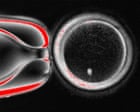

I ricercatori hanno creato uova umane a partire da cellule della pelle, potenzialmente trasformando il trattamento di fecondazione in vitro (IVF) per le coppie che non hanno altre opzioni.

Il lavoro è ancora in una fase iniziale, ma se i ricercatori potranno perfezionare il processo, potrebbe fornire uova geneticamente correlate per le donne che sono infertili a causa dell’età avanzata, di malattie o di trattamenti medici. La stessa procedura potrebbe essere utilizzata per creare uova per le coppie omosessuali maschili.

La tecnica utilizzata dai ricercatori consiste nel prendere cellule della pelle e trasformarle in cellule staminali, che possono poi essere indotte a diventare uova. Questo processo potrebbe rivoluzionare il trattamento della fertilità, offrendo nuove opzioni per le coppie che hanno difficoltà a concepire.